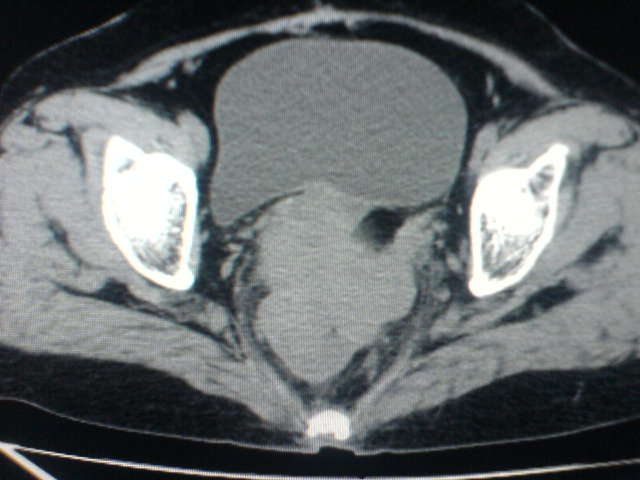

患者为老年女性,肿块最大层面不是位于宫颈,但宫颈偏后方有一囊状低密度影,肿块主要位于乙状结肠及直肠,所以考虑乙状结肠及直肠癌浸犯宫颈可能性大。

患者女性60岁 病史不详

宫颈癌侵犯直肠可能

考虑子宫内膜癌浸犯直肠。

考虑直肠癌侵及宫颈可能;建议增强扫描。

支持考虑宫颈癌上下前后通吃

考虑:直肠及乙状结肠癌侵及宫颈,囊性转移(假性粘液瘤)

支持宫颈癌侵犯直肠。

考虑直肠及乙状结肠癌侵犯邻近结构。